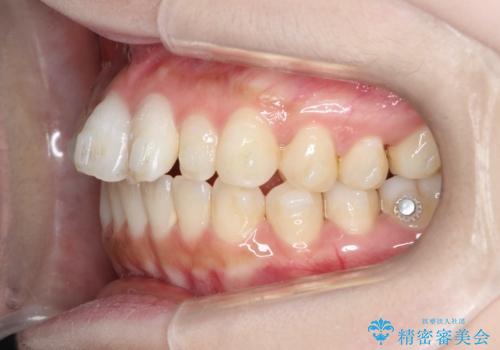

【インビザライン】矮小歯を有する方の治療②

- 前歯の凸凹を主訴に来院されました。

左上の前歯が元々小さいため、前歯の真ん中が揃わないことを伝えた上で矯正治療を開始しています。

スペースを作るために遠心移動ろIPRをおこなて治療を行いました。